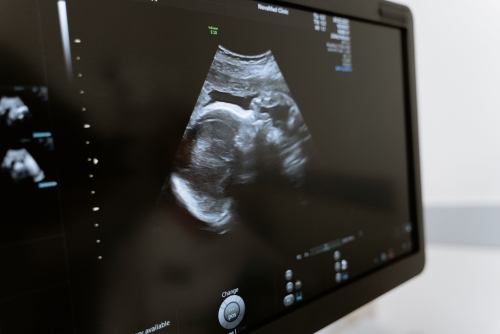

產前檢查通常在孕早期、孕中期、孕晚期進行,用于孕婦及胎兒的健康檢查。產前檢查一般包括四維彩超、胎兒彩超、糖尿病篩查、唐氏篩查等,應按照產檢要求及時進行相應檢查。

1、四維彩超:四維彩超在孕中期可用于篩查胎兒存在的各類畸形,如面部畸形、脊柱畸形、腦積水、唇腭裂、無腦兒、脊柱裂臟器外翻等。還可觀察到胎兒是否存在先天性心臟病,以及多囊腎、腎積水、腦積水、腦膜膨出、脊柱裂等疾病;

2、胎兒彩超:胎兒彩超可用于觀察胎兒的大小、形態、羊水、胎盤,以及胎兒是否存在臍帶繞頸等情況;